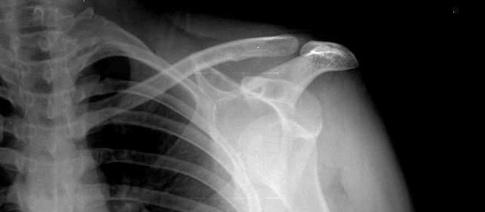

Prvotní vymknutí hlavičky kosti pažní je vždy doprovázeno rupturami (roztržením) kloubního pouzdra, defekty vazů, otokem a výraznou bolestivostí, výjimečné nejsou ani zlomeniny hlavice humeru či okrajů kloubní jamky.

K repozici v podmínkách zdravotnického zařízení se přistupuje v celkové či alespoň lokální anestezii, samozřejmě po kontrole na RTG. Následné znehybnění by nemělo být kratší než dva týdny. Zlomeniny musí být vždy řešeny operativně.

V článku jsem nepostřehl podstatnou maličkost. Při přímém úderu do ramene nebo do paže může dojít k poškození hlavice kosti pažní. Následné agresivní manévry s paží mohou způsobit poškození cév a nervů. Z posledních let mám zdokumentovány dva případy, které se navenek jevily jako obvykle vykloubené rameno. Podlitiny a následné RTG ukázaly poškození hlavice kosti pažní. Rozhodně nedoporučuji „nahazovat“ rameno u všech nárazů do paže a v okamžiku, kdy nemohu postiženého vizuálně zkontrolovat bez oblečení. Zde popisované agresivní metody repozice mohou způsobit nevratná poškození.